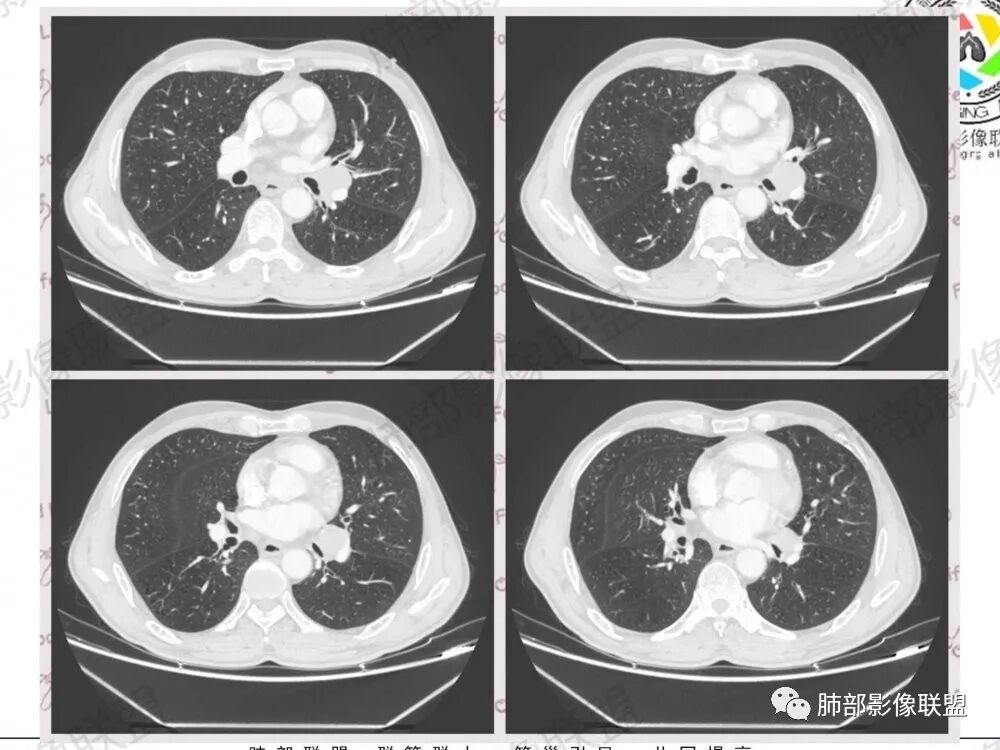

1.左肺门及纵隔见异常增大淋巴结,部分融合,不均匀轻度强化,未见明显坏死。

肿大淋巴结与纵隔血管等结构“无缝”贴合。

2.纵隔增宽但依旧居中。

2、小细胞癌恶性程度高,发展迅速,转移发生早;常有纵隔淋巴结的明显增大融合(发生率达96.5%),呈“冰冻纵隔”,淋巴转移常为逐站的连续性转移;亦有血行转移,脑、肾上腺、肝、胰、骨髓等;转移灶常比原发灶大得多,即“娘小崽大”特点;